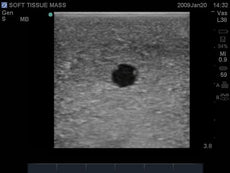

Gain proficiency in performing transvaginal ultrasound exams with our CAE Blue Phantom female pelvis models. The patented Simulex internal tissue allows learners to develop, practice and verify ultrasound imaging skills, including using ultrasound system controls, positioning and moving the transducer, recognizing internal pelvic anatomy and pathology and using gynecological ultrasound calculation packages to measure cysts, masses, and other structures. These models are excellent for 2D, 3D, and 4D ultrasonography imaging techniques. Choose from three options: General Pathology, Intrauterine & Ectopic Pregnancy, or Sonohysterographay & Sonosalpingography.